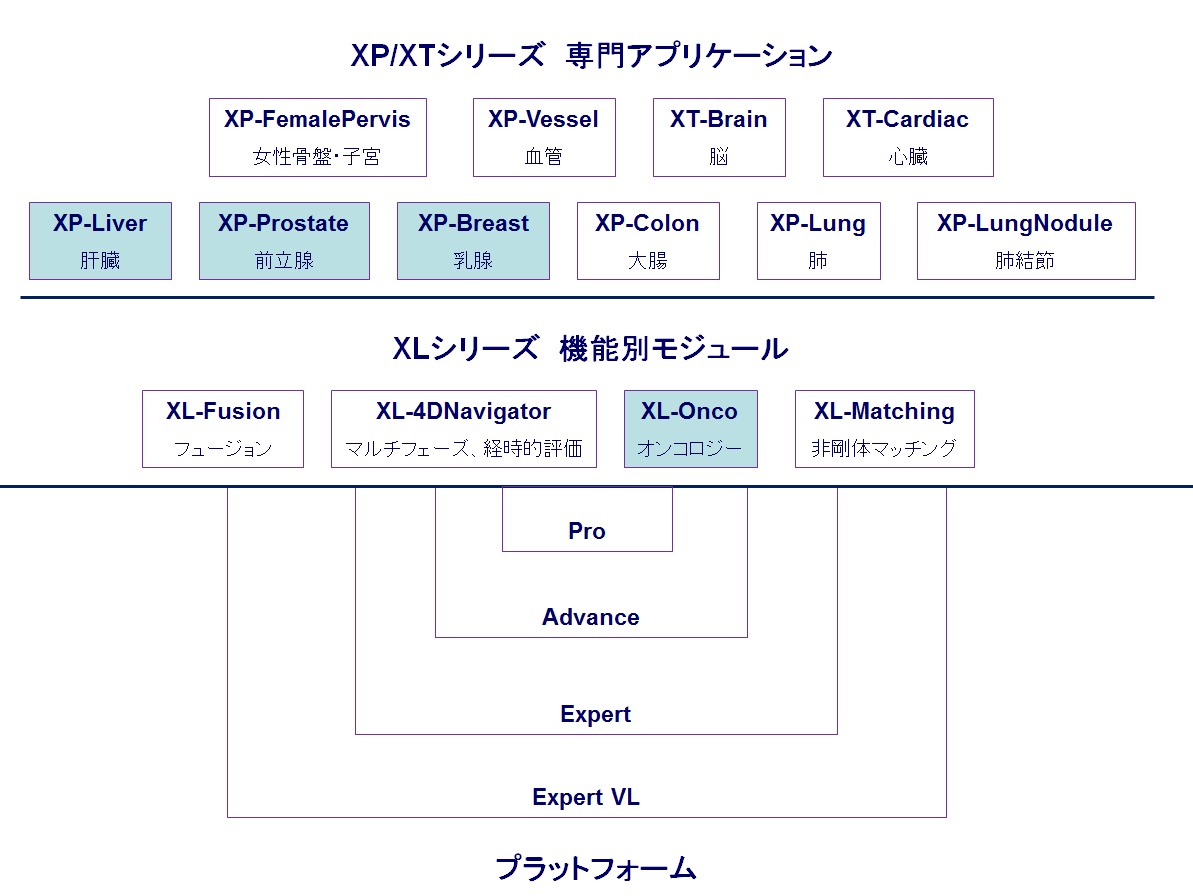

Myrian®

-高機能マルチモダリティ・プラットフォーム&専門アプリケーション-

Myrian®はメディカル・イメージング・ソフトウェア開発の世界的なエキスパートであるフランス、イントラセンス社により開発されました。2D マルチモダリティ・ビューアから3D/4D、3D PDFレポート機能まで、直感的な操作で機能ごと段階的に実装可能な高機能プラットフォームです。

XP , XT シリーズは専門化ニーズにお答えする、部位ごとに特化した先駆的なアプリケーション群です。そして、独自技術をベースにしたより高度な後処理(マルチモダリティ・フュージョン、3次元非剛体レジストレーソン、複雑なクリニカル・ワークフロー、その他より専門的なプロトコル)を実現する XL シリーズがあります。

下記のモジュールを機能/プロトコル単位でカスタマイズが可能です。

| ソフトウェア一覧 | |

|---|---|

| XL-Onco | 腫瘍の経時的フォローアップ |

| XP-Liver | 肝臓アプリケーション |

| XP-Prostate | 前立腺アプリケーション |

| XP-Breast | 乳腺アプリケーション |

| Advance | 基本機能のプラットフォームソフトウェア |

| ExpertVL | 最先端機能のプラットフォームソフトウェア |